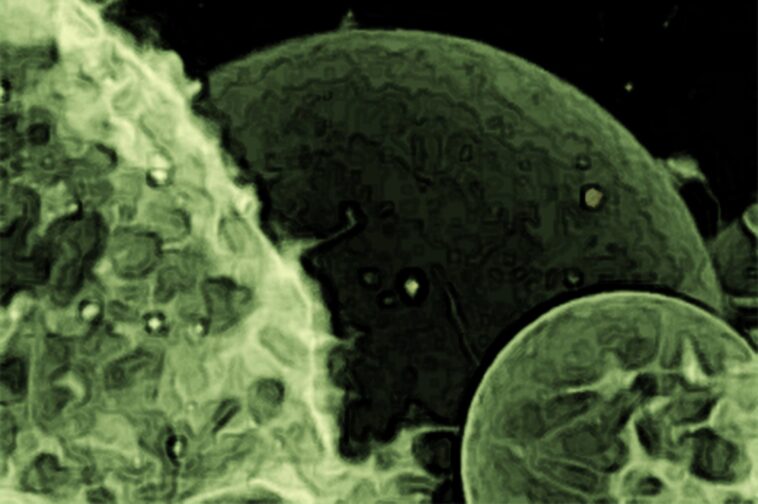

Des recherches récentes dirigées par Jerold Chun révèlent que les vésicules cérébrales des patients atteints de la maladie d'Alzheimer portent des instructions génétiques uniques qui peuvent contribuer à la progression de la maladie. L'étude a révélé une présence significative d'ARNm complets et un modèle d'expression génique unique associé à l'inflammation, offrant ainsi de nouvelles informations sur la pathologie d'Alzheimer et des pistes potentielles pour une détection et un traitement précoces. Ce portrait de vésicules extracellulaires a été réalisé par microscopie confocale à balayage laser. La membrane a été colorée avec un colorant fluorescent. Crédit : Tomaž Einfalt, Université de Bâle